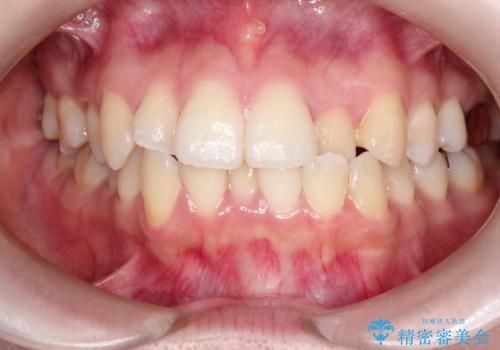

【ワイヤー矯正】口元を下げたい、下の歯の凹凸を無くしたい

- 主訴:口元を下げて前突感を無くしたい、下の歯の凹凸も無くしたい

骨格的顎の変位を認めたため、顔貌に対しピッタリ上下の歯の正中を合わせることは難しいと説明し、上下左右計4本小臼歯を抜歯しワイヤー矯正治療を行いました。